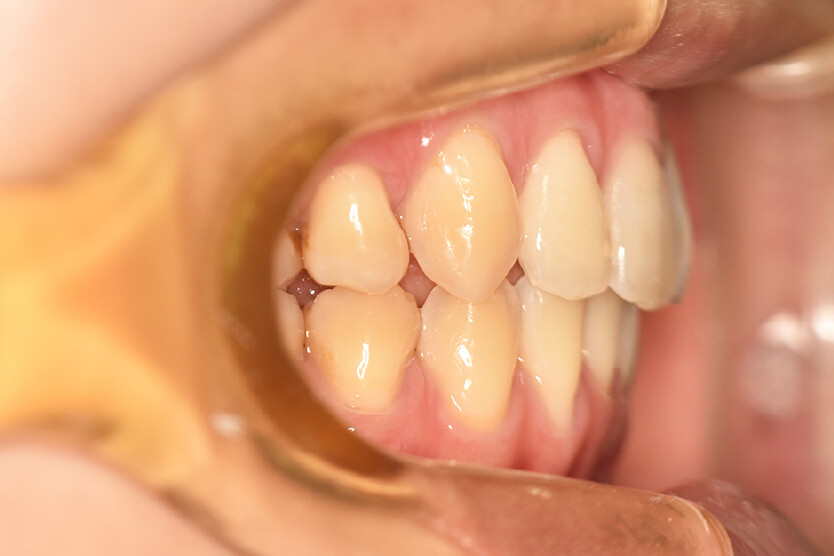

動的治療終了時

症例 症例 症例 症例

治療内容の詳細 初診時21歳の女性で、出っ歯、下顎前歯部のがたつきを気にされ来院されました。

検査の結果、上顎前突、上下顎前歯部叢生および開咬を伴うアングルⅡ級1類不正咬合と診断しました。

治療としては、上下左右第一小臼歯を抜歯して、セルフライゲーションブラケット装置(デーモンシステム)とマウスピース型矯正装置(インビザライン)で配列を行いました。

この際、上顎に歯科矯正用アンカースクリューを設置し上顎前歯部後退時の土台としました。

開咬については、顎間ゴムの協力もあり改善されました。